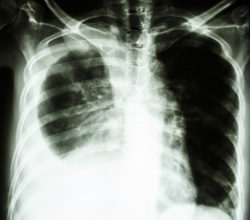

lung cancerCertainTeed has been hit with a lawsuit in which a widow alleges that her late husband’s asbestos-related lung disease was caused by exposure to asbestos in the company’s products.

According to plaintiff Joann Z., her husband Joseph Z. inhaled or was exposed to asbestos fibers from CertainTeed’s products at numerous points in his life, which led him to develop lung cancer and later resulted in his death.

The CertainTeed asbestos lung disease lawsuit states that Joseph Z. was diagnosed with lung cancer around Dec. 21, 2016. He passed away on Aug. 19, 2017. Joann Z. seeks damages of more than $50,000.